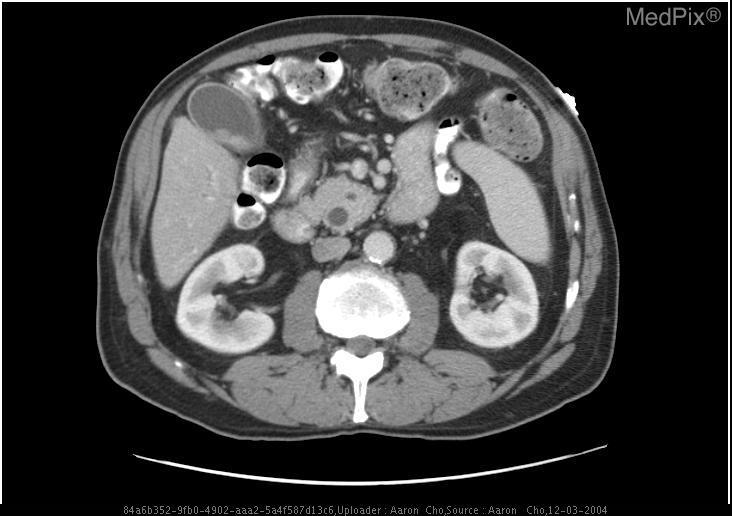

📌示例:针对如下影像,微调前后的输出

No.5 CT医疗诊断助手

模型“魔鬼训练”完毕,已经从“半吊子实习生”晋升为“专业医师助手”!那接下来,怎么让它真的派上用场?答案就是——构建医疗知识库 + RAG 检索增强生成,让模型不止会说,更能精准说!

我们来一步步操作,带你搭建一个属于你的CT医疗诊断助手,让模型不再孤军奋战,而是背后站着一整个医疗知识库做后盾!

📌整理知识库——医学资料大合集

我们选用Huatuo-Lite数据集(https://huggingface.co/datasets/FreedomIntelligence/Huatuo26M-Lite ),这是目前最大的中文医疗问答数据集,这些问答对通过文本清洗和数据去重的方法,从多个来源精心收集而来,包括在线医疗咨询网站、医学百科全书和医学知识库,覆盖了广泛的医疗知识。该数据集的创建显著扩大了医疗领域问答数据集的规模,并为中文医疗领域的自然语言处理和人工智能研究提供了一个前所未有的资源。

📌实现RAG——模型+知识双保险

🗝️原理:输入(用户带CT提问+微调后的VQA的初诊结果) → 向量检索相关医学知识 → 与输入拼接 → 喂给模型生成回答。

RAG 就像给模型配了「助理医生」,先去查资料,再结合自身能力回答,大大提升准确率和可信度。我们对输入的QA对进行拼接,并要求大模型根据提供的问题和CT影像的初步诊断结果,结合知识库召回结果进行回答:

📌效果展示

➡️input:下面是CT医疗问诊的问题以及CT图像初步诊断。问题:does the gallbladder appear distended?;图像初步诊断:yes;

➡️output:

可以看到小助手召回了相关片段并给出了回答!通过微调+RAG,LLM不再“闭门造车”,而是真正拥有了读万卷书 + 亲临临床的实力,成为你身边靠谱的AI医学助理!